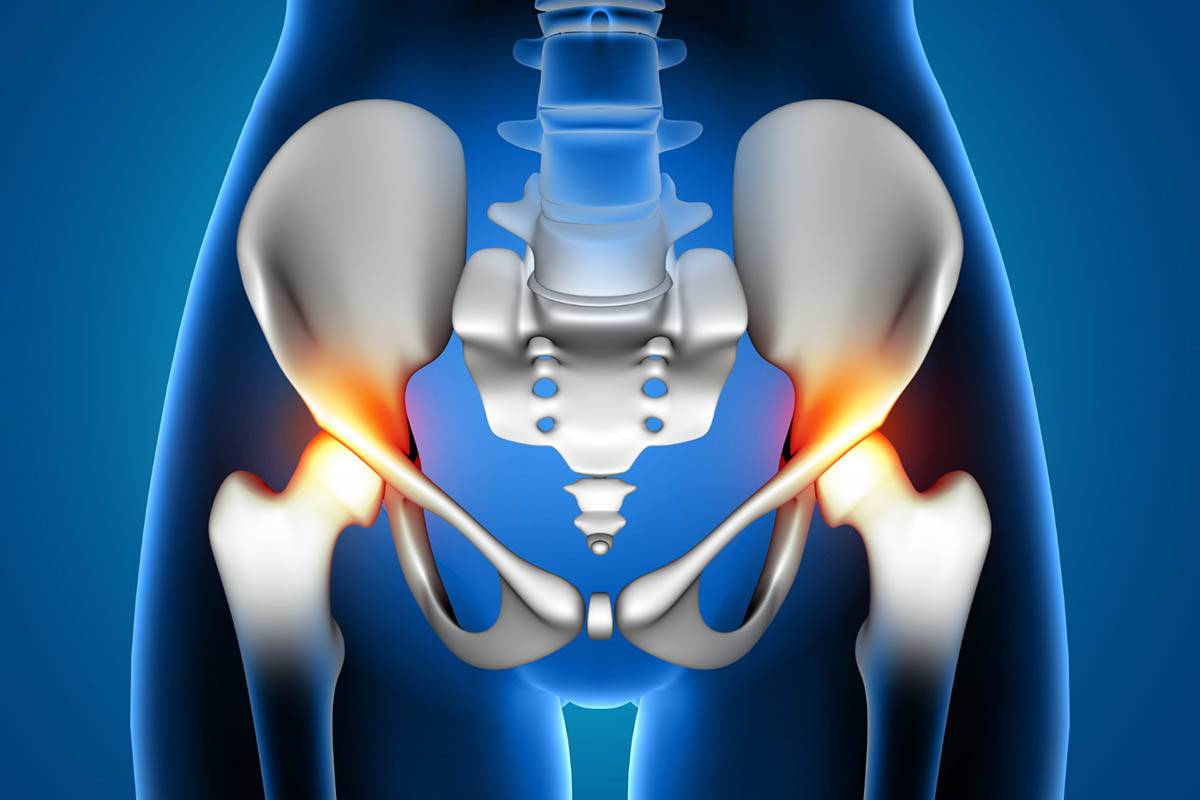

درگیری و آسیب مفصل لگن

علت صدا دادن مفصل ران و لگن